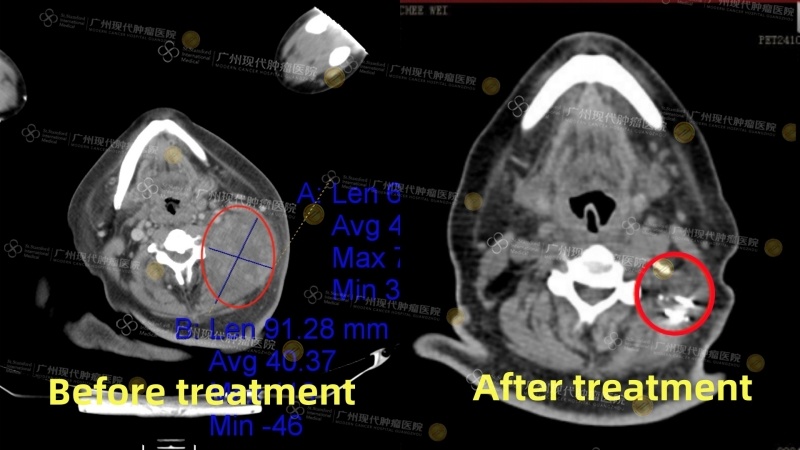

Tn. Chong Chee Wei dari Malaysia (kanker nasofaring) pada Oktober 2023 mengalami sakit kepala yang terus-menerus dan memutuskan untuk memeriksakan diri ke rumah sakit. Ia didiagnosis menderita kanker nasofaring stadium IV disertai metastasis ke kelenjar getah bening di leher, dengan diameter lesi terbesar mencapai 7,5cm. Di Malaysia, ia telah menjalani beberapa kali radioterapi dan kemoterapi, namun hasilnya kurang memuaskan. Berat badannya pun turun drastis sebanyak 30kg. Pada April 2024, ia datang ke Modern Cancer Hospital Guangzhou untuk menjalani pengobatan. Setelah menerima pengobatan komprehensif berupa terapi intervensi, terapi target, dan brachytherapy, tumornya menyusut hingga dua pertiga, dan kondisi fisiknya membaik secara signifikan. Kini, kondisi kesehatan Chong Chee Wei membaik secara nyata: tumornya mengecil secara drastis, berat badannya mulai naik kembali secara stabil, dan kondisi mentalnya juga pulih dengan baik.

Gambar perbandingan CT sebelum dan sesudah pengobatan Chong Chee Wei